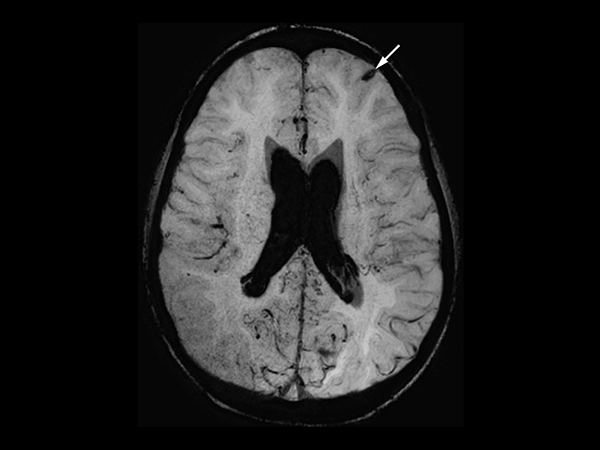

In this case, a 10-year-old girl thrown from a horse. The SWIp images provided increased visibility of the corpus callosum injury compared to the T2-weighted, diffusion weighted and gradient echo images, see the box in the images. SWIp also provides increased visibility of the cortical contusion (arrows) compared to gradient echo imaging. In this case, SWIp helped to characterize the extent of the patient’s injury, which is important to know for short term care and longer term prognosis and rehabilitation.

Axial SWIp